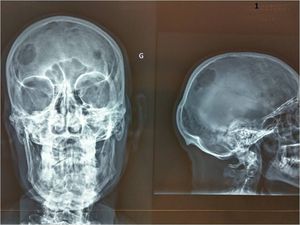

What is to worry about here ?

Meningioma?